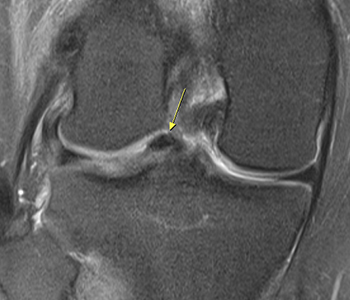

¹Ý¿ù»ó ¿¬°ñÆÇÀ̶õ ¹«¸°üÀý ³»¿¡¼

Çã¹÷Áö»À¿Í ÀåµýÁö»ÀÀÇ °üÀý¸é »çÀÌ¿¡ À§Ä¡ÇÏ¿©

üÁßÀü´Þ, ¿Ü·ÂÀÇ ºÐ»ê, °üÀý¿¬°ñ º¸È£, °üÀýÀÇ ¾ÈÁ¤¼º ¹× À±È°±â´É µîÀÇ Áß¿äÇÑ ±â´ÉÀ» °¡Áö°í ÀÖ´Â ±¸Á¶¹°ÀÔ´Ï´Ù. ÇϳªÀÇ ¹«¸ ¾È¿¡ ³», ¿ÜÃø µÎ °³°¡ Á¸ÀçÇϴµ¥, ÀÌ·± ¹Ý¿ù»ó ¿¬°ñÆÇÀÇ ÆÄ¿Àº ¹«¸ÀÌ »ì¦ ±¸ºÎ·¯Á® ÀÖ´Â »óÅ¿¡¼ µÚƲ¸®¸é¼ ¹ß»ýÇÏ°Ô µË´Ï´Ù.